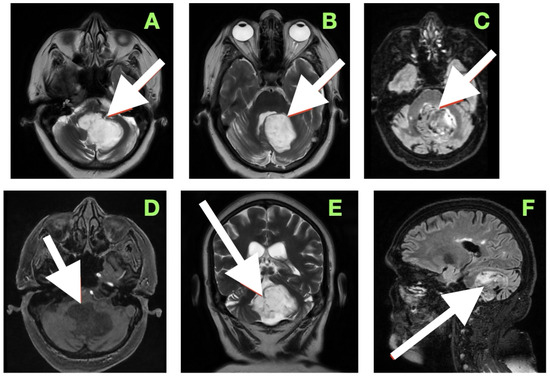

Background: Gorlin syndrome (GS) is a rare autosomal dominant disorder, associated with pathogenic PTCH1 or SUFU variants, predisposing to tumors such as basal cell carcinoma, medulloblastoma (MB), odontogenic keratocyst, and, rarely, cardiac fibroma (CF). MB occurs in ~5% of GS cases, typically in [...] Read more.

Background: Gorlin syndrome (GS) is a rare autosomal dominant disorder, associated with pathogenic PTCH1 or SUFU variants, predisposing to tumors such as basal cell carcinoma, medulloblastoma (MB), odontogenic keratocyst, and, rarely, cardiac fibroma (CF). MB occurs in ~5% of GS cases, typically in early childhood, while CF appears in 1–3%. Their coexistence in childhood is extremely rare. This report describes a pediatric GS case with synchronous MB and CF, focusing on the management priorities between oncologic and cardiac interventions. Methods: A 15-year follow-up is reported for a girl diagnosed at 22 months with desmoplastic/nodular MB and left ventricular CF. GS diagnosis was based on clinical features, imaging, and confirmation of a pathogenic PTCH1 variant (c.3306+1G>T). A literature narrative review on CF in GS was also conducted. Results: MB gross total resection was followed by chemotherapy, during which ventricular tachycardia episodes occurred, managed with cardioversion and antiarrhythmics. Given the favorable prognosis of early-treated MB in GS, oncologic therapy was prioritized. Cardiac status was monitored with ECG, Holter, echocardiography, and cardiac MRI. An adapted AIEOP protocol minimized cardiotoxicity. CF was managed conservatively, with no further arrhythmias and preserved ventricular function throughout 15 years. MB has not recurred. Conclusions: In GS patients with concurrent MB and CF, prioritizing MB treatment and adopting a conservative, closely monitored approach to CF can yield excellent long-term outcomes. In children with MB, especially syndromic forms, routine echocardiography is recommended to detect CF. This case underscores the value of multidisciplinary care in managing complex GS presentations. Full article

Show Figures

Figure 1